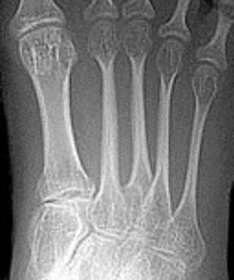

| Describe the alignment of metatarsal 2 | There is no angulation nor displacement of the distal segment relative to the proximal segment. |

| Describe the alignment of metatarsal 3 | The distal segment is displaced laterally (50% apposition) and angulated medially. |

| Describe the alignment of metatarsal 4 | The distal segment is displaced laterally (75% apposition) but there is no apparent angulation. |

| Describe the tubulation of the metatarsals | Metatarsals are overtubulated - decreased girth. |

| Describe the tubulation of the metatarsals | Metatarsals are undertubulated - increased girth. |